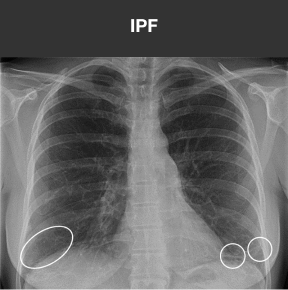

HRCT is the standard in diagnosing ILD9

HRCT allows for the recognition of fibrosis and other abnormalities that may not be apparent on chest x-ray. Below is a comparison of imaging from a 43-year-old female with 3 weeks of sinus congestion and clear sputum production after running:

Case study used with permission from the American Thoracic Society.

Recognizing pulmonary fibrosis early on HRCT is critical18-20

When ILD is suspected in the primary care setting, consider follow-up evaluation by a pulmonologist. Early referral can enable early access to HRCT and multidisciplinary evaluation, the key to early and accurate diagnosis of fibrotic ILDs.